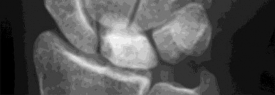

Which of the following describes the correct vascular anatomy and blood supply of the scaphoid, predisposing its proximal pole to avascular necrosis following fracture?

Options:

- The primary blood supply enters at the dorsal ridge and supplies the proximal pole via retrograde flow.

- The primary blood supply enters the proximal pole directly from the anterior interosseous artery.

- The primary blood supply enters the volar tubercle and supplies the bone via antegrade flow.

- The ulnar artery provides the dominant supply to the proximal pole via the deep palmar arch.

- The dorsal carpal branch of the radial artery enters the proximal pole directly.

Correct Answer: The primary blood supply enters at the dorsal ridge and supplies the proximal pole via retrograde flow.

Explanation:

The major blood supply to the scaphoid (70-80%) comes from branches of the radial artery that enter the bone via the dorsal ridge (near the waist) and perfuse the proximal pole in a retrograde fashion. Because of this retrograde flow, fractures at the waist or proximal pole can disrupt the blood supply to the proximal fragment, greatly increasing the risk of avascular necrosis and nonunion.